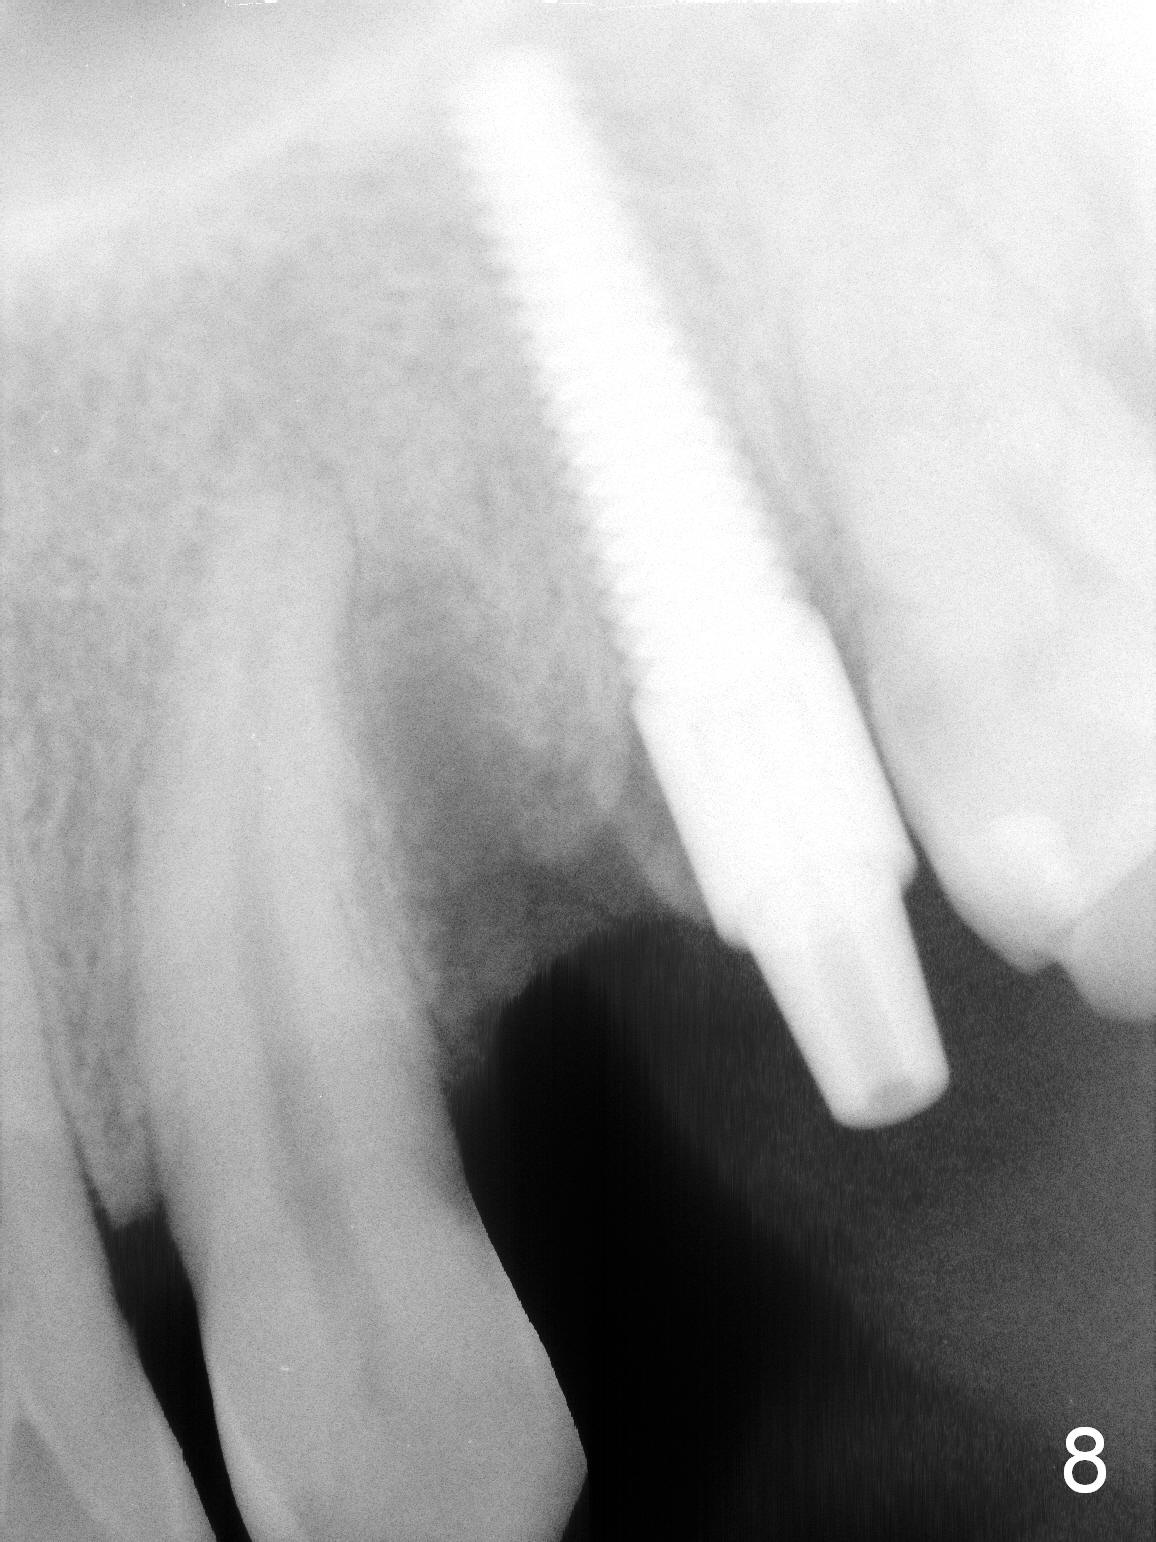

Taking 2 additional PAs with sensor 1 is frustrating (Fig.1,2), no apices shown. Osteotomy is done smoothly with 2 mm pilot drill at 20 mm, 2.5 mm reamer at 17 mm, and 3 mm reamer at 14 mm and 4.5x20 mm tap at 17 mm. The 1st intraop PA is taken with sensor 1 when 2 of 4.5x20 mm implants are placed (Fig.3); the implant at #12 is close to the root of the tooth #11. The 2nd PA is taken with sensor 2: the apex of #11 touches the implant at #12 (Fig.4). There is no separation when panoramic X-ray is taken (Fig.5). Effort is exerted to re-direct the osteotomy twice (Fig.6: tap; Fig.7: implant) without success. When the implant is removed, a PA is taken; it appears that the root of the tooth #11 has no damage (Fig.8). To obtain the best recovery, socket preservation is carried out with 50/50 cortical/cancellous allograft mixed with Osteogen (Fig.12 *) and Collagen Dressing (Fig.9: #12). A 2 (or 3)-unit provisional bridge (Fig.10: #12,13) is fabricated over the implant (Fig.9 I)/abutment (A) to cover these 2 sockets. After acid etching #11 D surface (Fig.9 >) and relining (Fig.11 *), the provisional bridge is bonded to the tooth #11 (Fig.11,12 black >) so that bone graft will be less likely dislodged.